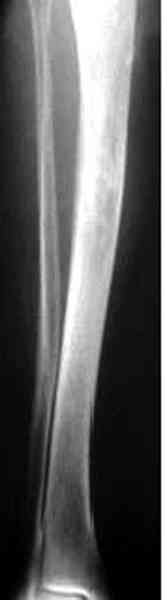

Недавно на нашей ежемесячной Morbidity&Mortality conference мы

разбирали похожий случай, ложный сустав большеберцовой кости после

резекции опухоли.

К нашему онкологу-ортопеду обратился больной с жалобами на боли в

голени, из рассказа - год назад была сделана биопсия большеберцовой

кости, но название заболевания "не запомнил".

Имя     : 1 adamantioma ap orig.jpg